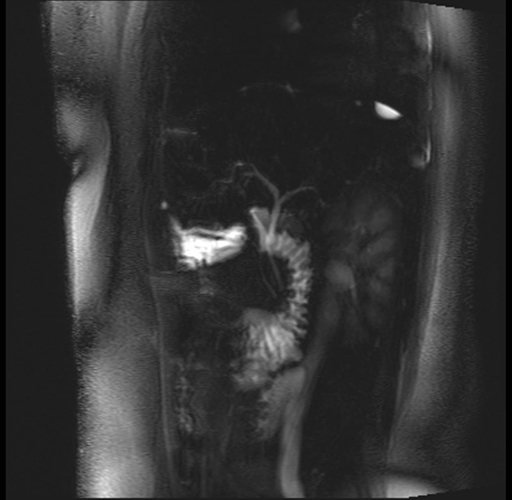

Imaging Analysis

Look through the patient's CT scan to identify any areas of concern for the necessary procedure.

Based on your CT findings, which issue(s) are present and would give reason for "planned slowing down moment(s)" in this case?

Considering a standard distal pancreatectomy procedure, what step(s) of the operation would you do differently in this case?